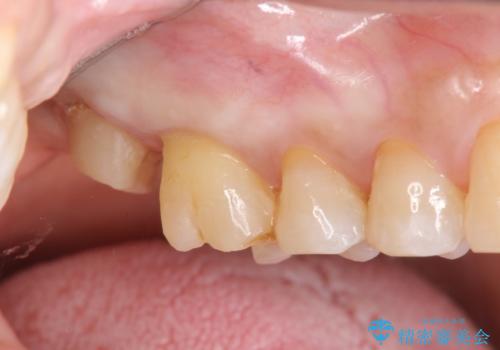

歯髄方向 歯肉方向へと深い 2種類の大きな虫歯

#17は失活歯で歯肉方向への縁下カリエス、#16は生活歯であるものの歯髄ギリギリの処置となるであろうとが予想される治療です。